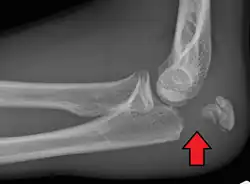

To assess an olecranon fracture, a careful skin exam is performed to ensure there is no open fracture. Then a complete neurological exam of the upper limb should be documented.[5][2] Frontal and lateral X-ray views of the elbow are typically done to investigate the possibility of an olecranon fracture.[1] A true lateral x-ray is essential to determine the fracture pattern, degree of displacement, comminution, and the degree of articular involvement.

Olecranon fracture is a fracture of the bony portion of the elbow. The injury is fairly common and often occurs following a fall or direct trauma to the elbow. The olecranon is the proximal extremity of the ulna which is articulated with the humerus bone and constitutes a part of the elbow articulation. Its location makes it vulnerable to direct trauma.